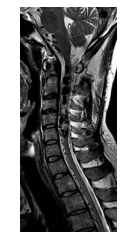

A 15-year-old boy presents with neck pain and bilateral upper limb weakness. MRI is shown below.Which one of the following is most likely?

e. Type III juvenile (extradural-intradural) AVM

Juvenile spinal AVMs are extremely rare lesions.

These lesions are again true AVMs, with an intramedullary niduswhichmay occupy the entire spinal canal at the involved level. Cord tissue is present within the AVM interspaces. Extramedullary and even extraspinal extension of the lesion is possible.

Juvenile AVMs are large and complex lesions, with

multiple arterial feeding vessels often arising from

different cord levels. Hemodynamically, this lesion

manifests both high flow and high pressure, often

yielding an auscultatable spinal bruit over involved

levels. They occur most commonly in adolescents

and young adults. Presentation and treatment are

similar to Type II AVMs; however, prognosis for

these lesions, considering their size and vascular

complexity,is understandably very poor.MRimaging typically demonstrates prominent flow voids

suggestive of underlying vascular malformation.

Edema or gliosis can also be seen on MR imaging